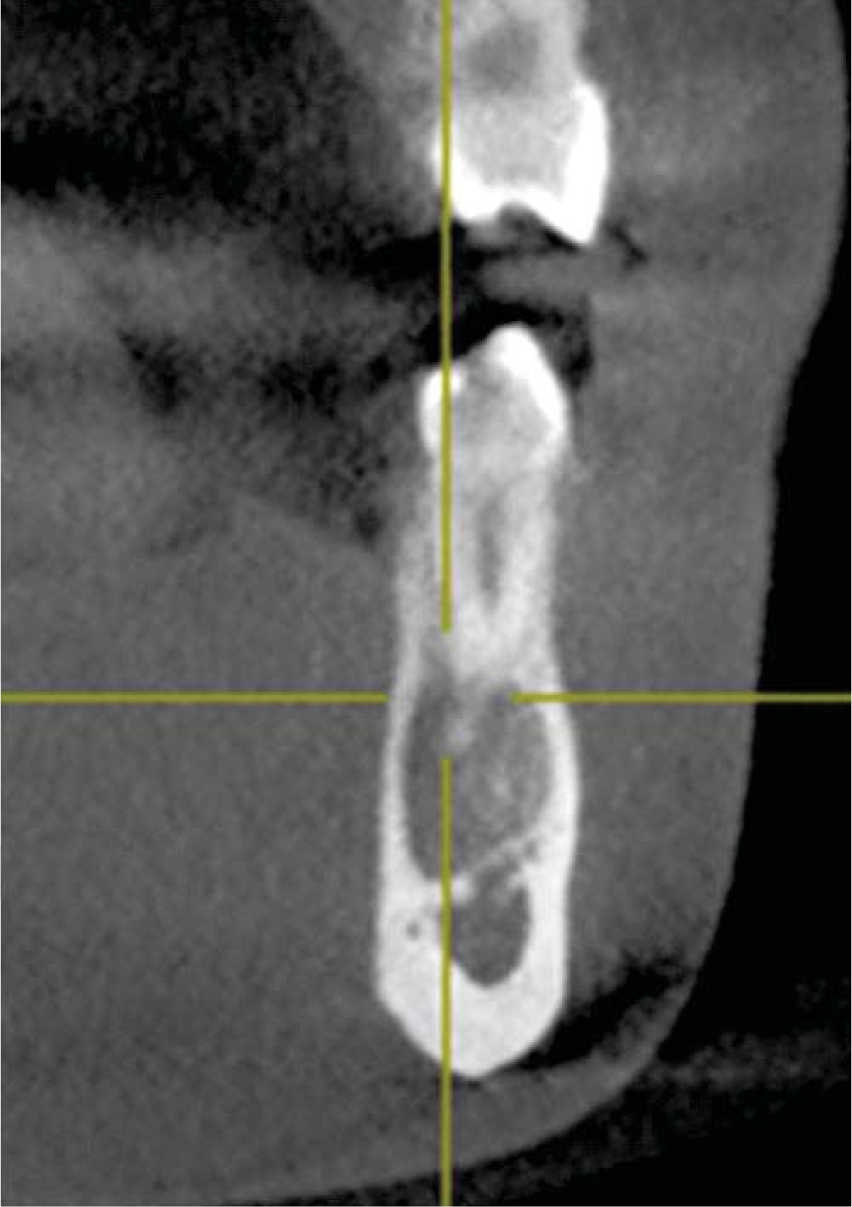

Orthopantomography revealed a radio-lucid lesion, with an irregular border and radio-opaque halo. The lesion involved first premolar, second premolar, and lower left canine, no root resorption or displacement was observed. The lesion exhibited a festooned border in the area of involved dental roots (Figures 2 and 3) and did not present expansion of cortical bone, nevertheless it exhibited thinning in lingual and vestibular cortical bone (Figure 4).

Figure 4 Cross-sectioned cut of the lesion showing thinning of lingual and vestibular cortical bone, without exhibiting expansion.

The lesion extended along the mandibular body without causing bone expansion; lower buccal and lingual cortical bone became thinner (Figure 4). There was no displacement of adjacent teeth towards the lesion; teeth responded positively to vitality tests. These data concur with those reported by Chrcanovic's30 and Xanthinaki's11 clinical case studies. Microscopic study revealed trabecular bone lacking significant histological data, such as mentioned by Harnet et al.9